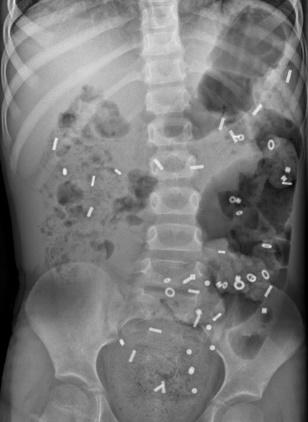

- Röntgenfoto van de buik: Hiermee kan worden bekeken hoe ernstig de verstopping is. Soms wordt dit gecombineerd met een markerstudie, waarbij uw kind capsules inneemt om de snelheid van de ontlasting te meten.

Coloninloop: Dit is een onderzoek waarbij contrastvloeistof via het poepgat wordt ingebracht om de dikke darm beter te bekijken. Daarna worden er een aantal röntgenfoto's na elkaar gemaakt, zodat de darm goed te zien is. Zo kan de arts goed beoordelen of de darm lang, wijd of kronkelig is.- Als uw kind dit spannend vindt, kan een medisch pedagogisch zorgverlener u en uw kind helpen om ervoor te zorgen dat dit proces zo soepel mogelijk verloopt.

- Röntgenfoto: Beeld van de binnenkant van het lichaam, gemaakt met straling.

- Coloninloop: Onderzoek waarin de dikke darm zichtbaar wordt gemaakt met vloeistof en rontgenfoto’s.